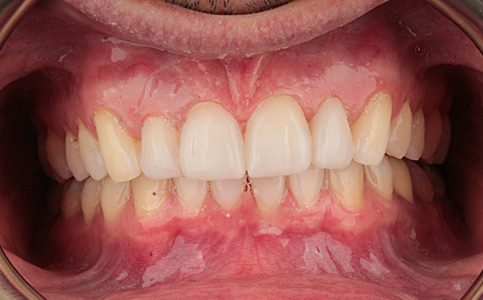

Pacjent zgłosił się do naszej kliniki ponieważ marzył o pięknym uśmiechu. Jego metamorfoza była wielospecjalistyczna. Pierwszym etapem było leczenie biologiczne, następnie uzupełnienie braków zębowych implantami oraz wykonanie koron pełnoceramicznych na zęby górne. Dzięki temu Pacjent odzyskał pewność siebie i zdrowy uśmiech.